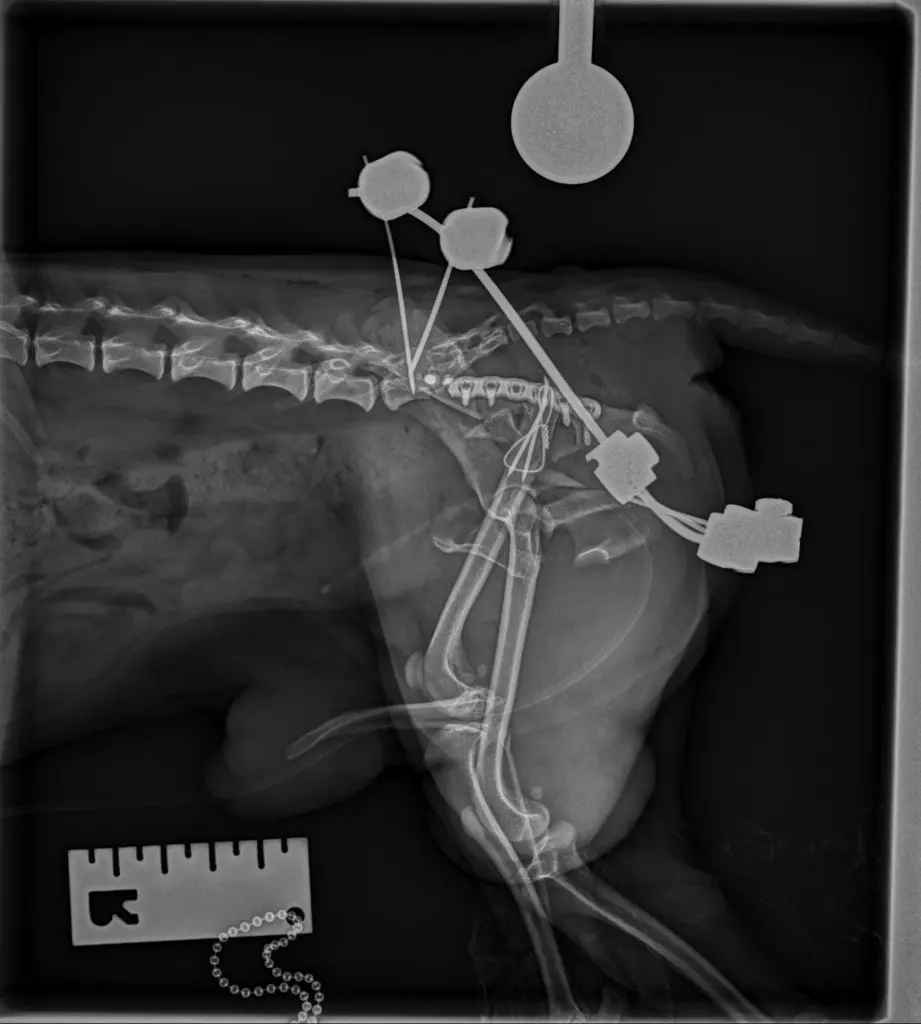

Para obtener un diagnóstico definido, procedimos a realizar un protocolo diagnóstico completo, que incluyó un estudio radiológico y tomográfico de la pelvis. Gracias a las imágenes pudimos confirmar el diagnóstico, una fractura múltiple de pelvis con luxación sacroiliaca derecha, y luxación coxofemoral izquierda a consecuencia de una fractura conminuta del acetábulo.

Para poder definir con mas precisión todos los daños y establecer el mejor plan quirúrgico realizamos una tomografía computarizada (TAC) de la pelvis.